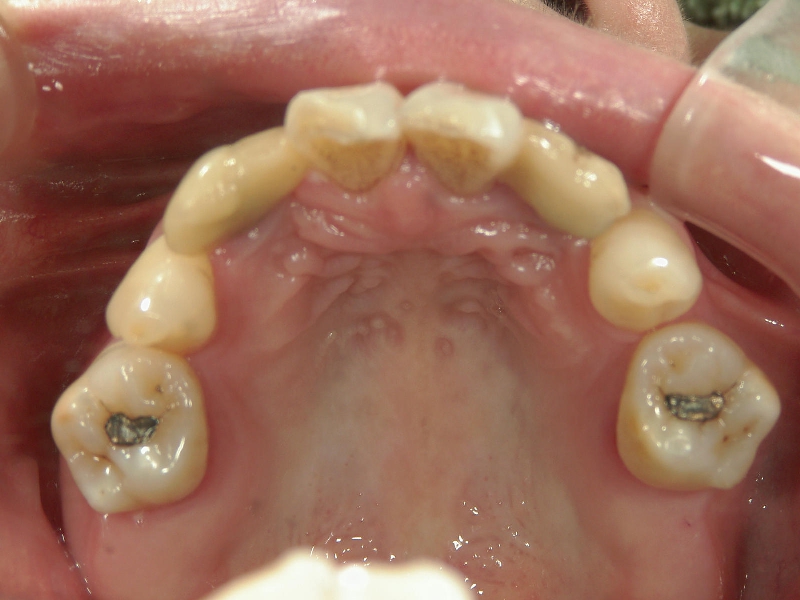

● 臼歯部の後方移動

臼歯を後方に牽引し、移動させることでスペースを確保し歯列を整えます。

抜歯矯正をした経験があり、新たに抜歯

できる歯がないため、臼歯を後方へ牽引

してスペースを確保します。

臼歯にリンガルアーチという装置を装着し、ミニインプラントを固定源に臼歯を後方に牽引します。

前突が改善し、きれいな歯並びになりました。

臼歯が後方に下がり、臼歯と小臼歯の間にスペースができました。唇側にワイヤ-をSETし、前歯の歯並びの改善を併行して行います。